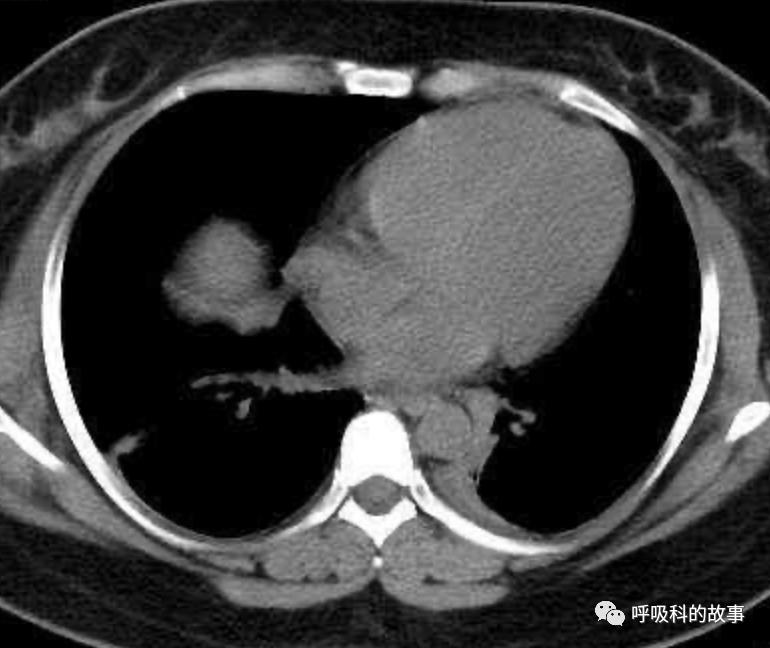

患者发热后行胸部CT检查(6月21日,住院第13天),可见两下肺有条片影,当时考虑是肺炎引起的发热。

可是在6月26日(往院第18天)仍持续发热的情况下复查肺部CT,肺部病灶已明显吸收了。那么患者发热的原因到底是什么呢?为什么患者高热的情况下血白细胞不升反降,C反应蛋白也没有明显增高?这个时候消化科医生也迷茫了,这可怎么办?于是请感染科和呼吸科医生一起会诊,共商计策。